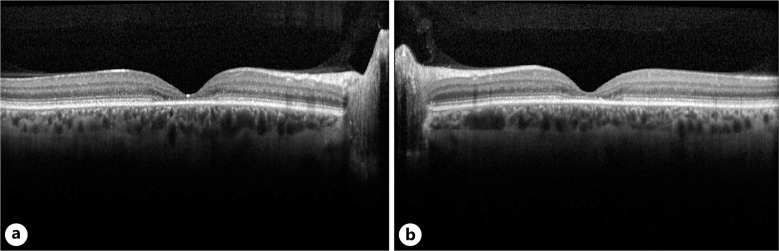

Case presentation: A 47-year-old male with progressive vision loss exhibited symptoms indicative of maculopathy. These included decreased central vision, visual distortions, photophobia, poor depth perception, glare, impaired dark/light adaptation, difficulty reading, depressed multifocal ERG responses, and central ellipsoid dropout on SD-OCT. Evaluation included genetic testing, segregation analysis, and a complete ophthalmic examination, including slit-lamp exam, dilated fundus exam, FAF, SD-OCT, ERG, and Humphrey 24-2 visual fields. A 351 gene retinal dystrophy panel revealed two variants in MFSD8, including one pathogenic variant (c.1006G>C, p.Glu336Gln) and one likely pathogenic variant (c.291G>C, p.Trp97Cys), confirmed to be in trans via segregation testing.